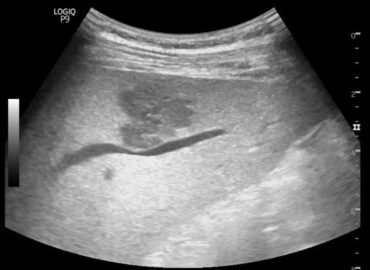

Mujer, 32 años, dolor abdominal

Mujer de 41 años con fiebre sin foco